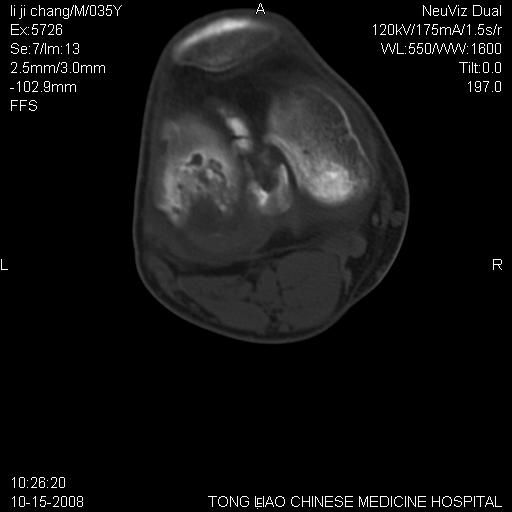

男,35岁,骨科诊断骨性关节炎。继往使用过激素,现股骨头坏死。膝关节病变,请会诊

一元论-----亦考虑为坏死

支持考虑无菌坏死

支持无菌坏死伴退行性骨关节病.

剥脱性骨软骨炎:是一种关节下软骨及软骨下骨缺血性坏死。

支持 无菌性坏死伴退行性骨关节病。